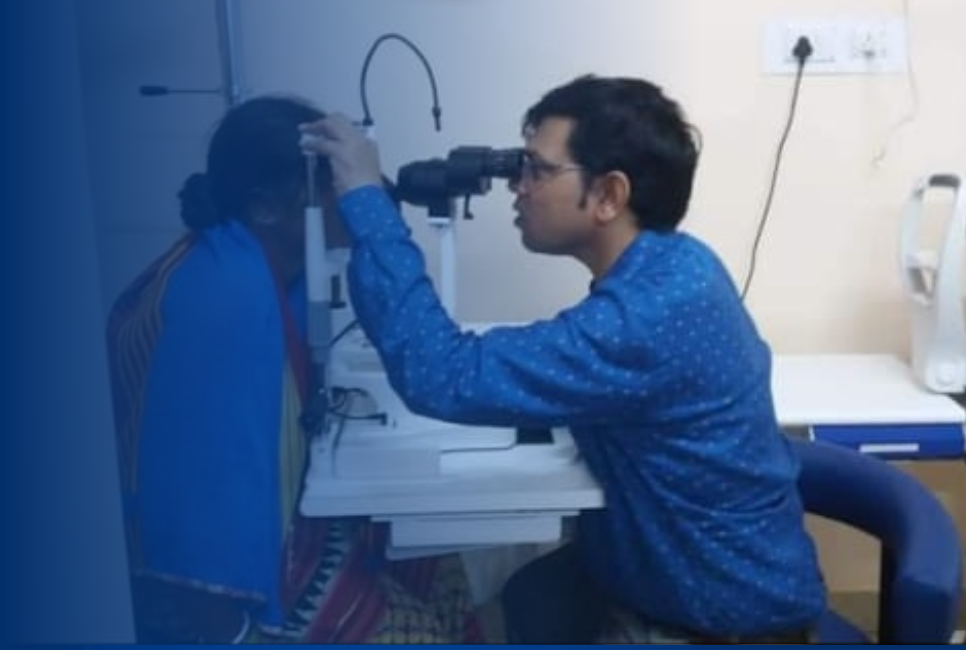

Consultation & Check-Up

Every visit begins with a detailed vision test and discussion to understand your eye health and visual needs.

Accurate Diagnosis

Our experts use advanced tools to identify the exact cause and design a suitable treatment plan for you.